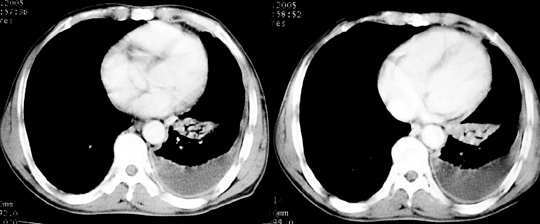

以下是引用jiajie在2005-11-6 22:07:00的发言:[br]1)左肺下叶阻塞性肺炎,胸腔积液,中心型肺癌可能大,建议纤支镜。[br]2)结合30年打石史,双肺弥漫性小结节考虑矽肺。

以下是引用sdqzwyx在2005-11-7 19:59:00的发言:[br]双肺弥漫大小不等的粟粒状结节影;肺纹理走行失去自然,粗细不均,边缘不规则,小叶间隔增厚;左上肺示不规则形致密影,从斑块边缘向周围伸出长短不一的致密索条影,临近的血管、支气管和叶间胸膜等结构受牵拉移位;左下肺示不规则团块状影,其内示空洞,洞内壁尚光整,左侧胸腔积液。右肺下叶背段亦示部分病灶融合。双肺可见局限性肺气肿。[br]诊断:结合病史符合三期矽肺表现(少数矽肺纤维斑块内可以形成空洞,一般认为是斑块中央感染引起坏死所致)但尘肺病人易合并肺结核,诊断可为三期+tb。所以此病人应进一步检查是否合并结核。